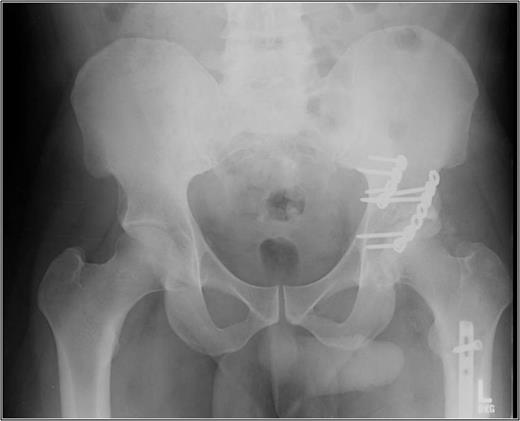

AP pelvis 8 months status post-ORIF of posterior wall with retrograde femoral nail. The left hip demonstrates early post traumatic arthritis and heterotopic ossification.